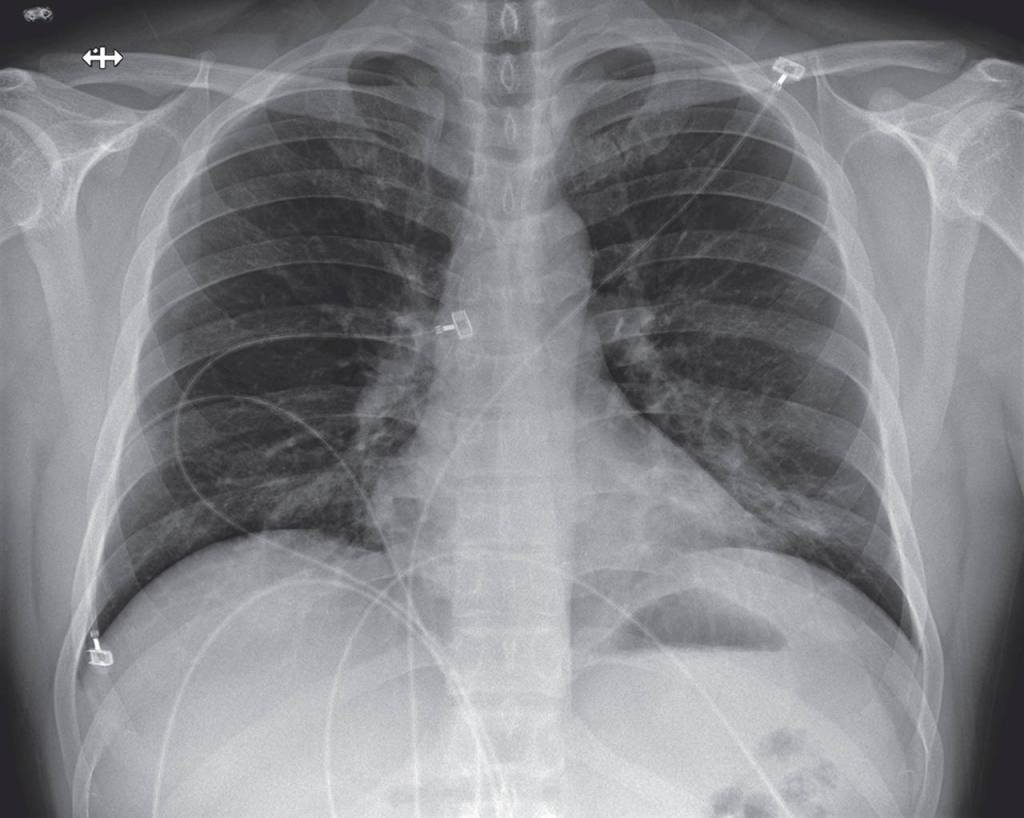

The article details the patient’s symptoms — everything from fatigue, nausea, diarrhea to a runny nose — over time and graphs his lab results. It shows X-rays of his lungs.